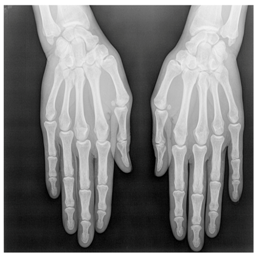

In this section, we present and analyze the results obtained with the proposed method, and compare it to methods proposed in similar works. The proposed watermarking system is implemented using MATLAB and executed on a Windows machine with the following characteristics: Intel R Core i5 processor, 4 GHz, 4 GB RAM, and Microsoft Windows 8 Professional operating system platform. In our experiments, we have used DICOM images of size 512 × 512 pixels as shown in Table 1.

Table 1.

Original images.

In our method, several copies of the watermark are embedded in the RONI region, and the ROI region is kept intact. ROI and RONI are separated using the method presented in Section 3.2. The watermark is inserted in the RONI using a linear interpolation technique. From the results, one can see that there is no significant visual difference between the original and the watermarked images. Nevertheless, the difference appears through the values of SSIM and PSNR presented in next subsection.